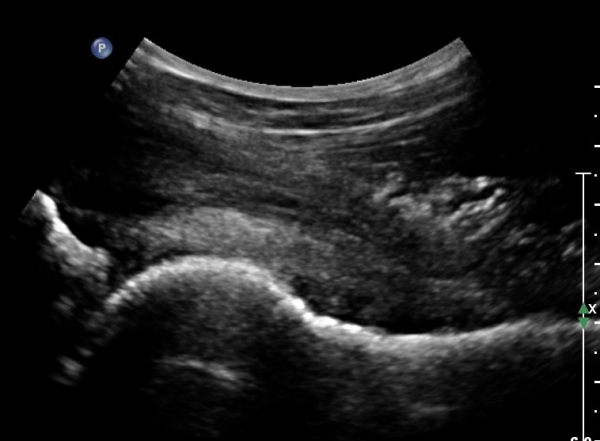

°í°üÀý À§, ¿ÜÃø¿¡¼­ ´ëÅðÁ÷±Ù Á¾´Ü¸é°Ë»ç»ó  ´ëÅðÁ÷±Ù °ðÀº ¼¶À¯(direct) ±â½ÃºÎ¿¡ ¹Ì¼¼ÇÑ

¼®È¸¼º º´º¯À» º¸À̳ª ÈûÁÙÀÇ Àú¿¡ÄÚ ºÎÁ¾Àº °üÂûµÇÁö ¾ÊÀ½.(»çÁø 3, 4)